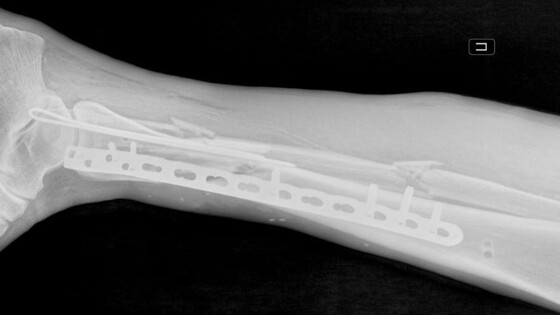

У пострадавшего были диагностированы перелом костей правой голени со смещением, рваная рана бедра и обширная рана левой голени. В больницу мужчину доставили вместе с плугом культиватора. На момент поступления нога была холодной и посиневшей, кровь в конечность не поступала.

«Мы провели срочную операцию, в ходе которой промыли раны и закрепили отломки костей правой голени в анатомически правильном положении с помощью аппарата внешней фиксации. Также восстановили кровоток и устранили сдавление сосудов», — рассказал врач-травматолог-ортопед Игорь Кучерявый.